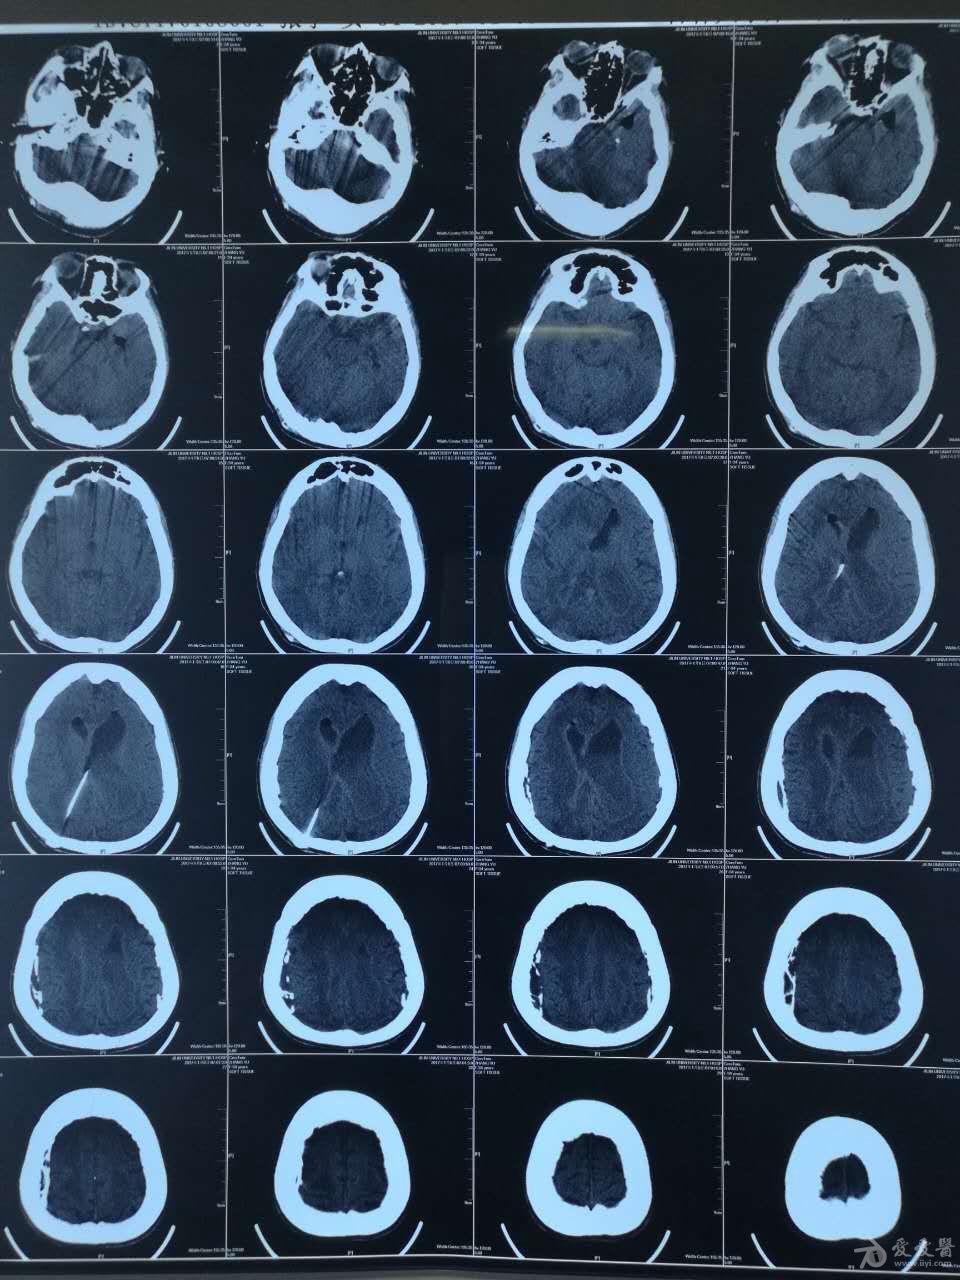

脑积水ct显示:侧脑室,三脑室扩大有症状的脑积水应该及时手术治疗.

李春志 男 64 脑积水 3-2脑室腹腔分流

交通性脑积水(正常颅压性脑积水)vp分流治疗一例

脑积水一例